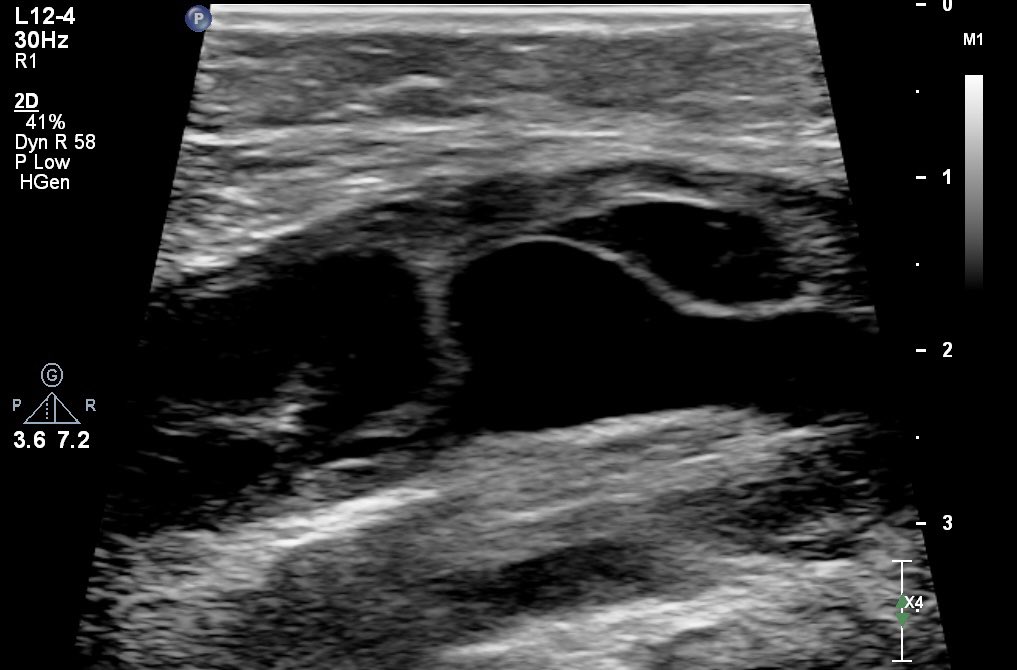

Dilated left intergemellar vein with reflux

(P.S.: The small saphenous vein was atrophic).

#vascularultrasound